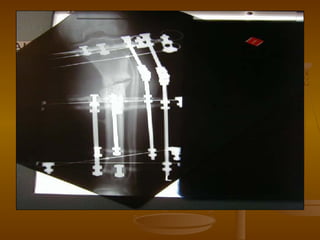

Ex-FixEx-Fix

 Self-tapping pinsSelf-tapping pins  local heatlocal heat

 thermal necrosis &thermal necrosis &

microcracking (thusmicrocracking (thus

corrosion/fatigue)corrosion/fatigue)

 Pin MicromotionPin Micromotion  bonebone

resorption at interfaceresorption at interface

 Undersize hole 0.1 mmUndersize hole 0.1 mm  decrdecr

micromotionmicromotion

 Undersize >0.3 mmUndersize >0.3 mm  incrincr

microcrackingmicrocracking

 Deformation of Pin or Side BarDeformation of Pin or Side Bar

 Stiffness & Strength proportional to diameterStiffness & Strength proportional to diameter44

 Stiffness & Strength inversely proportional to lenghtStiffness & Strength inversely proportional to lenght33

 To increase strength:To increase strength:

 Decrease sidebar to bone distanceDecrease sidebar to bone distance

 Increase pin diameterIncrease pin diameter

 Put pins closer to fracturePut pins closer to fracture

 Increase # of sidebarsIncrease # of sidebars

 Bury pin thread completely within cortexBury pin thread completely within cortex

 Add Sidebar at 90 degree plane also resist torsionAdd Sidebar at 90 degree plane also resist torsion